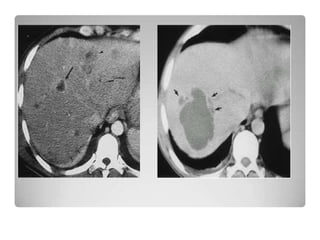

IMAGENOLOGÍA

TAC:

•Método de elección para detectar

lesiones hepáticas

• Visualiza el hígado en su totalidad.

• TAC con técnica helicoidal trifásica

detecta lesiones de 0.5 cm.

• Permite observar abscesos en hígado

graso y tiene una sensibilidad y

especificidad del 95%.

Catalano, O. et al. Am. J. Roentgenol. 2004;182:447-450

--39-year-old woman with right upper quadrant pain and leukocytosis